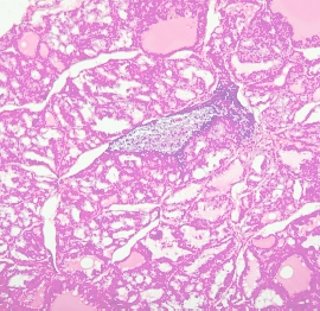

Pathology 病理學

Pathology is the study of diseases. It is a bridging discipline involving both basic science and clinical practice. The aspects of a disease process that form the core of pathology are its cause, the mechanisms of its development, the structural changes, and the consequences of the morphologic change.

病理學主要在研習各種疾病時,人體內細胞、組織、器官及全身各部在結構上與功能上之傷害與影響;探討疾病之病源、致病機轉、病發時之主要症狀與病徵,及病變過程與預後等等,本課程為一學年,本學期二學分,以講演方式教授,每週共二小時。本學期在課程最後安排複習課程。